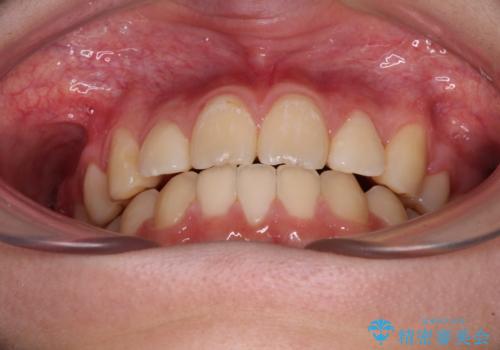

目立つ八重歯を治したい インビザラインによる矯正治療

- 目立つ八重歯を改善したいとのことで来院された患者様です。

奥歯の咬み合わせは左右とも理想的なものでしたが、下顎前歯が1本欠損しているため、上下のバランスを保つことが難しい歯列でした。

唇を閉じたときに上顎前歯が下顎の唇に乗っかる印象があったため、八重歯の後方にある小臼歯を1本抜歯することとしました。

変則的な抜歯となるため、臼歯の咬合が理想的でなくなることが懸念されますが、インビザラインにて矯正治療を行うこととしました。